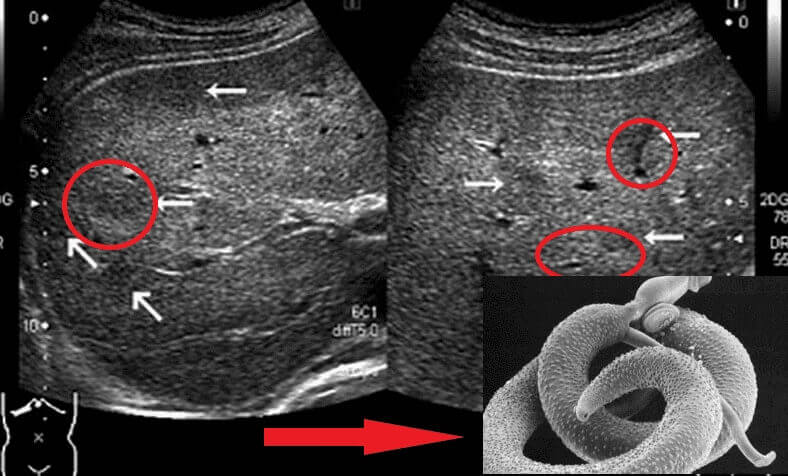

รูของพยาธิ ในลำไส้

ผมทำงานเป็นนักพยาธิวิทยามานาน ผมเห็นอะไรมาเยอะมาก คนส่วนใหญ่ประมาทและชะล่าใจอันตรายจากพยาธิ พวกเขาคิดว่าพยาธิก็แค่มองเห็นเป็นตัวๆอยู่ในลำไส้ แต่จริงๆ แล้วมีพยาธิหลายชนิดมาก บางชนิดตัวเล็กมากจนมองไม่เห็นด้วยตาเปล่า แต่มีพิษร้ายแรง พวกมันจะปล่อยสารพิษเข้าสู่ร่างกาย เข้าไปในกระแสเลือด เข้าไปในหัวใจ ทำให้เกิดภาวะขาดเลือด หัวใจล้มเหลว ความดันโลหิตสูง และนำไปสู่โรคหัวใจวายและโรคหลอดเลือดสมอง พวกมันยังสามารถเข้าไปในปอด ตับ และแม้แต่ในสมองและไปอาศัยอยู่ในดวงตาได้อีกด้วย

พวกพยาธิที่เข้าทำลายอวัยวะสำคัญ ได้แก่ พยาธิตัวตืดหมู (Taenia solium), พยาธิตัวตืดหมา (Echinococcus granulosus), และพยาธิไตรคิเนลลา (Trichinella spiralis) โดยพยาธิตัวตืดหมาเป็นตัวอ่อนของพยาธิในสกุล Echinococcus และนี่เป็นเพียงส่วนหนึ่งของพยาธิหลายชนิดที่สามารถฆ่าคนได้